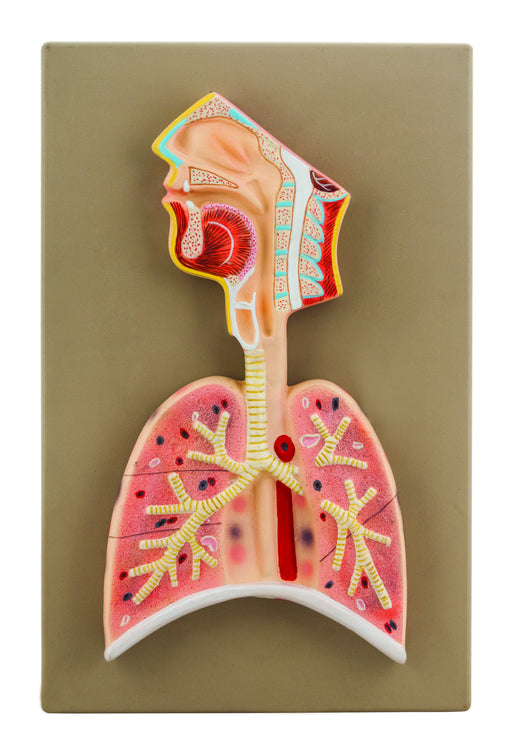

Eisco Labs Human Respiratory System Model, Half Live Size, Longitudinal Section of Head, Throat and Lungs

Approximately 1/2 life size longitudinal section of head, throat and lungs, 14" tall x 6.5" wide Illustrates respiratory organs and structures inc...

View full detailsAM0278 -